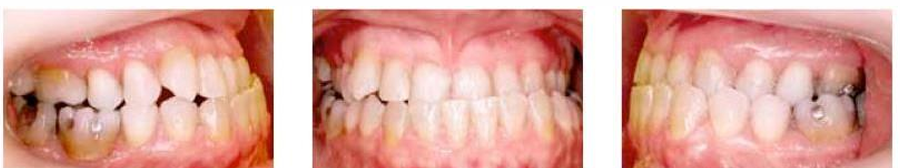

MFD EXAMS /23 6 1234567891011121314151617181920212223 You have 30 min to complete this exam. The timer will start once you begin Attention: Only a few minutes left! Please submit your answers soon. MFD 1 Get a quick sneak peek before the real exam !This trial quiz is designed to show you the question style, difficulty level, and how the options will appear on the platform. 1 / 23 1. What is the lethal dose and toxic dose of fluoride, management? Check 2 / 23 2. What the advantage of silver diamine over other methods and disadvantages ? Check 3 / 23 3. Method of topical fluoride application with concentration ? Check 4 / 23 4. What will happen if left untreated? Check 5 / 23 5. What changes that will happen if the habit stopped? Check 6 / 23 6. Give 3 of your initial stage of treatment? Check 7 / 23 7. What are the causes? Check 8 / 23 8. What is this? Check 9 / 23 9. Then they specified the type of pain and asked about the diagnosis Check 10 / 23 10. What other tests to check vitality of the pulp? Check 11 / 23 11. What are the factors will govern the Rx of Posterior cross bite ? Check 12 / 23 12. What are the factors that govern the treatment of anterior cross bite? Check 13 / 23 13. Name the appliance that you can use to treat this case? Check 14 / 23 14. Name 3 causes? Check 15 / 23 15. Name the most important clinical diagnostic information you need to know. (check RCSI intensive course )? Check 16 / 23 16. What do you see? Check 17 / 23 17. What is your treatment? Check 18 / 23 18. Name the investigations needed? Check 19 / 23 19. causes for gingival enlargement ? Check 20 / 23 20. What is the common side effect of this drug? Check 21 / 23 21. Name the drug that he may take to treat this condition? Check 22 / 23 22. The patient may have what? Check 23 / 23 23. What is this clinical condition? Check /31 2 12345678910111213141516171819202122232425262728293031 You have 30 min to complete this exam. The timer will start once you begin Attention: Only a few minutes left! Please submit your answers soon. MFD 2 Get a quick sneak peek before the real exam !This trial quiz is designed to show you the question style, difficulty level, and how the options will appear on the platform. 1 / 31 1. Mention 2 fixed space maintainers and 2 removable space maintainers other from mentioned : Check 2 / 31 2. Other space maintenance used for child lost primary second molar E before the eruption of the permanent molars ? Check 3 / 31 3. What are the difference between nance appliance and Transpalatal arch Check 4 / 31 4. What material used to attach band? Check 5 / 31 5. What instruction you give to patient? Check 6 / 31 6. Name other fixed space maintainer used in upper jaw and mechanism of their action? Check 7 / 31 7. What component of this appliance? Check 8 / 31 8. What is this appliance , for what its used ? Check 9 / 31 9. Treatment? Check 10 / 31 10. Define Abrasion and Erosion? Check 11 / 31 11. What does this picture show? Check 12 / 31 12. what investigations you can do ? Check 13 / 31 13. Drugs can lead to lichenoid reaction Check 14 / 31 14. What extra oral features in “ Lichenoid reaction )? Check 15 / 31 15. What microscopical features of it ( licheonoid reaction )? Check 16 / 31 16. Definitive diagnosis ? Check 17 / 31 17. Mention type of suggested biopsy ? Check 18 / 31 18. Mention 4 differential diagnosis ? Check 19 / 31 19. Mention 4 questions you will ask the patient ? Check 20 / 31 20. Give 4 intraoral decription of what you see ? Check 21 / 31 21. What the other surgery can be performed to make prothesis? Check 22 / 31 22. Can this tooth stand with fixed prothesis? (in the opg )à taken from Malek file ? Check 23 / 31 23. Radiograph of missing multiple teeth consider it according to Antes law? ON which tooth you will make Abutment ? Check 24 / 31 24. What is Antes law? Check 25 / 31 25. What is best one to use as abutment in fixed prosthesis A or B? Check 26 / 31 26. What relevance of this picture? Check 27 / 31 27. What’s complication of doing surgery in this area floor of mouth? Check 28 / 31 28. Other 2 radiograph needed in diagnosis? Check 29 / 31 29. Give 4 differential diagnosis? Check 30 / 31 30. What can you see ? Check 31 / 31 31. What is the name of radiograph? Check Your score is /30 1 123456789101112131415161718192021222324252627282930 You have 30 min to complete this exam. The timer will start once you begin Attention: Only a few minutes left! Please submit your answers soon. MFD 3 Get a quick sneak peek before the real exam !This trial quiz is designed to show you the question style, difficulty level, and how the options will appear on the platform. 1 / 30 1. Treatment? Check 2 / 30 2. Histopathology? Check 3 / 30 3. Differential diagnosis Check 4 / 30 4. Clinical features’? Check 5 / 30 5. Patient said, this lesion is very frequent, why? Check 6 / 30 6. What are the causes for ulcers? Check 7 / 30 7. Patient have other signs like uveitis ,Genital ulcerations which syndrome he had ? Check 8 / 30 8. Name of the lesion ? Check 9 / 30 9. Mention some TMJ movement ? Check 10 / 30 10. Blood supply ? Check 11 / 30 11. Nerve supply ? Check 12 / 30 12. Which muscles close? Check 13 / 30 13. Action of open and open wide? Check 14 / 30 14. Why it’s Atypical joint ? Check 15 / 30 15. Name of the ligaments ? Check 16 / 30 16. What would be your management? Check 17 / 30 17. Bacteria involved Check 18 / 30 18. Which type of Periodontitis? Check 19 / 30 19. Treatment? Check 20 / 30 20. Histopathology? Check 21 / 30 21. Differential diagnosis? Check 22 / 30 22. Clinical features? Check 23 / 30 23. What are the time frames for making a complaint? Check 24 / 30 24. What are the 3 points related to negligence? Check 25 / 30 25. Who is allowed access to the patient records? Check 26 / 30 26. How to differentiate if it is upper or lower motor neuron lesion? Check 27 / 30 27. Management? Check 28 / 30 28. What are the causes? Check 29 / 30 29. What should you advise the patient to do? Check 30 / 30 30. What is this lesion? Check Your score is /24 1 123456789101112131415161718192021222324 You have 30 min to complete this exam. The timer will start once you begin Attention: Only a few minutes left! Please submit your answers soon. MFD 4 Get a quick sneak peek before the real exam !This trial quiz is designed to show you the question style, difficulty level, and how the options will appear on the platform. 1 / 24 1. What does MRONJ stands for? Check 2 / 24 2. Give definition for MRONJ Check 3 / 24 3. For what medical problems these medications are used? Check 4 / 24 4. Stages of MRONJ 3 Check 5 / 24 5. What’s this appliance? Check 6 / 24 6. At what age is it used? Check 7 / 24 7. What type of malocclusion is it used to treat? Check 8 / 24 8. What changes will produce? (4 options) Check 9 / 24 9. Disadvantages? Check 10 / 24 10. Why is it flabby tissue? Check 11 / 24 11. what is this condition called? Check 12 / 24 12. Causes ? Check 13 / 24 13. Clinical Features ? Check 14 / 24 14. How to avoid it ? Check 15 / 24 15. Management? Check 16 / 24 16. Ideal post length and width Check 17 / 24 17. Definition of Ferrule it’s the Check 18 / 24 18. What is the importance of the ferrule effect ? Check 19 / 24 19. Describe the radiolucency? Check 20 / 24 20. Give 6 differential diagnosis? Check 21 / 24 21. Give 5 radiographical features? Check 22 / 24 22. What is the difference between incisional and excisional biopsy? Check 23 / 24 23. What other 2 plain radiographs we can we can take? Check 24 / 24 24. ALARA? Check Your score is /22 1 12345678910111213141516171819202122 You have 30 min to complete this exam. The timer will start once you begin Attention: Only a few minutes left! Please submit your answers soon. MFD 5 Get a quick sneak peek before the real exam !This trial quiz is designed to show you the question style, difficulty level, and how the options will appear on the platform. 1 / 22 1. . Types of external root resorption? Check 2 / 22 2. The cause of root resorption in the pic? Check 3 / 22 3. How you will treat it? Check 4 / 22 4. What is this probe? Check 5 / 22 5. What is the mark a ? Check 6 / 22 6. What is the mark b ? Check 7 / 22 7. What is the score from the given reading? Check 8 / 22 8. What is the treatment need of the patient according to the score? Check 9 / 22 9. What is the differential diagnosis ? Check 10 / 22 10. Four clinical features of the lesion? Check 11 / 22 11. Treatment ? Check 12 / 22 12. Describe what do you see? Check 13 / 22 13. Causes for it ? Check 14 / 22 14. Treatment ? Check 15 / 22 15. Picture of patient with Anaphylaxis…after taking Check 16 / 22 16. What is diagnosis? - Check 17 / 22 17. What a the signs of Anaphyalxis reactions ? Check 18 / 22 18. What first line of treatment? Dose? Route of Adminstration? Check 19 / 22 19. Other drug used? Check 20 / 22 20. What are expected complications if not treated ? Check 21 / 22 21. What precautions should be made to prevent anaphylaxis reaction ? - Check 22 / 22 22. Name 10 drug in emergency used with their route of Administration and their condition they use in? Check Your score is /36 1 123456789101112131415161718192021222324252627282930313233343536 You have 30 min to complete this exam. The timer will start once you begin Attention: Only a few minutes left! Please submit your answers soon. MFD 6 Get a quick sneak peek before the real exam !This trial quiz is designed to show you the question style, difficulty level, and how the options will appear on the platform. 1 / 36 1. . What are cases that you have to extract the primary tooth? Check 2 / 36 2. D. What are the indications for extraction? Check 3 / 36 3. What are your treatment options? Check 4 / 36 4. Investigations? Check 5 / 36 5. Type of trauma? Check 6 / 36 6. Patient diagnosed with sjorgen syndrome Histology ? - Check 7 / 36 7. Patient diagnosed with sjorgen syndrome Mention four blood investigations ? Check 8 / 36 8. Patient diagnosed with sjorgen syndrome Mention two sites where can we take the biopsy Check 9 / 36 9. Patient diagnosed with sjorgen syndrome How can you differentiate between primary and secondary ? Check 10 / 36 10. Gingival inflammation present in which syndrome Check 11 / 36 11. What is the treatment? Check 12 / 36 12. mention another connective tissue disease that can lead to lesions “ intraorally “ similar to the Lichen planus ? Check 13 / 36 13. what serious complication can arise from Erosive lichen planus ? Check 14 / 36 14. If it was atrophic lesion what histology might be seen ? Check 15 / 36 15. List the histological features of lichen planus ? Check 16 / 36 16. Lichen planus what dose it affect? Check 17 / 36 17. Age group commonly affected ? -ref SAQ Check 18 / 36 18. What are the clinical presentation ‘ types of lichen planus ‘ Check 19 / 36 19. What might you see in patient’s body that has a relation to this lesion? Check 20 / 36 20. What are the differential diagnoses? Check 21 / 36 21. Factors for platelet adhesion? Check 22 / 36 22. What can you see? Check 23 / 36 23. Other 2 process of hemostasis? Check 24 / 36 24. Two diseases in which they increase ? Check 25 / 36 25. Two diseases in which they decrease? Check 26 / 36 26. Medical term when they decrease? And if they increased Check 27 / 36 27. Function Check 28 / 36 28. Life span ? Check 29 / 36 29. From where they arise? Check 30 / 36 30. Normal number? Check 31 / 36 31. What are the function of the guiding plane ? Check 32 / 36 32. The success rate ? Check 33 / 36 33. Mention single extra preparation requirement for Resin bonded bridge in posterior teeth ? Check 34 / 36 34. Mention 5 preparation features of it? Check 35 / 36 35. Give two advantages of it ? Check 36 / 36 36. What’s the name of this prosthesis? Check Your score is /23 1 1234567891011121314151617181920212223 You have 30 min to complete this exam. The timer will start once you begin Attention: Only a few minutes left! Please submit your answers soon. MFD 7 Get a quick sneak peek before the real exam !This trial quiz is designed to show you the question style, difficulty level, and how the options will appear on the platform. 1 / 23 1. If the same scenario but the tooth is subluxated. What is the management? Check 2 / 23 2. Aim of this procedure Check 3 / 23 3. Steps to do this procedure? Check 4 / 23 4. Management? How to asses the vitality of the tooth Check 5 / 23 5. Mention factors that can affect the treatment plan ? Check 6 / 23 6. Identify the Kenneyd’s classification Check 7 / 23 7. Name its parts? Check 8 / 23 8. Uses of Surveyor Check 9 / 23 9. What is this ? Check 10 / 23 10. Criteria for hand piece sterilization Check 11 / 23 11. steps for wrapped instrument sterilization process ( ref : sterilization in SDCEP)? Check 12 / 23 12. What is the difference between sterilization and decontamination? Check 13 / 23 13. Optimal temperature & pressure & time for autoclave? Check 14 / 23 14. Difference between vacuum and non-vacuum autoclave in mechanism? Check 15 / 23 15. Optimum temperature? Check 16 / 23 16. Advantage of vaccum over non vaccum? Check 17 / 23 17. What is the significance of forehead wrinkling? Check 18 / 23 18. What is Ramsy haunt syndrome ? Rx ? and is it LMN or UMN ? Check 19 / 23 19. Enumerate 3 extracranial and intracranial causes for this ? Check 20 / 23 20. What are the branches of facial nerve? Check 21 / 23 21. Why do we suture the eye in a patient with Facial Palsy? Check 22 / 23 22. Differentiate between Upper and Lower Motor Neuron lesions? Check 23 / 23 23. What is shown in photograph? Check Your score is /27 0 123456789101112131415161718192021222324252627 You have 30 min to complete this exam. The timer will start once you begin Attention: Only a few minutes left! Please submit your answers soon. MFD 8 Get a quick sneak peek before the real exam !This trial quiz is designed to show you the question style, difficulty level, and how the options will appear on the platform. 1 / 27 1. Mention 4 diseases you would see in HIV Patients? Check 2 / 27 2. Give 2 differential diagnosis for this lesion? Check 3 / 27 3. Describe the lesion shown in Photograph B? Check 4 / 27 4. What is your diagnosis ? Check 5 / 27 5. Describe the lesion shown in Photograph A? Check 6 / 27 6. Disadvantages of gold ? Check 7 / 27 7. Ideal cement for All Porcelain? Check 8 / 27 8. Which cement would u use for high caries risk patient? Check 9 / 27 9. How much would you prepare for functional and non-functional cusps in Gold Crown? Check 10 / 27 10. what crown would you go for in bruxism patients out of these 3? Check 11 / 27 11. Name the 3 restorations? Check 12 / 27 12. After administering Local Anesthesia and deciding the choice of biopsy. What should be done before biopsying the lesion? Check 13 / 27 13. Name 2 systemic steroids with dosage you would recommend for this patient? Check 14 / 27 14. Name 2 topical steroids with dosage you would recommend for this patient? Check 15 / 27 15. What is your diagnosis? Check 16 / 27 16. Describe the lesion shown in photograph? Check 17 / 27 17. Name 5 options to increase retention and stability in class l Check 18 / 27 18. E. What is the function of the RPI system ? Check 19 / 27 19. What are the 2 disadvantages of the 2 restorations you mentioned? Check 20 / 27 20. What materials are your 2 restorations made of? Check 21 / 27 21. Other than implants what restoration would you place in this patient? Check 22 / 27 22. Which Kennedy’s classification is this? Check 23 / 27 23. Describe your management? Check 24 / 27 24. What may be the patient complaint? Check 25 / 27 25. What are the causes of this? Check 26 / 27 26. Describe what you see in the photograph? Check 27 / 27 27. which 4 examinations would you undertake? Check Your score is /31 0 12345678910111213141516171819202122232425262728293031 You have 30 min to complete this exam. The timer will start once you begin Attention: Only a few minutes left! Please submit your answers soon. MFD 9 Get a quick sneak peek before the real exam !This trial quiz is designed to show you the question style, difficulty level, and how the options will appear on the platform. 1 / 31 1. Describe what you see in the photograph? Check 2 / 31 2. Three other features of this syndrome ? Check 3 / 31 3. What is the medical condition associated with it “? Multiple OKC? Check 4 / 31 4. Where expansion occurs in the OKC ? Check 5 / 31 5. From which cells this lesion arises from? Check 6 / 31 6. What is your diagnosis? Check 7 / 31 7. What is the histopathology of the lesion shown in Histology slide? Check 8 / 31 8. Give 4 differential diagnosis? Check 9 / 31 9. What is the consequence of premature loss of deciduous teeth? Check 10 / 31 10. Identify those appliances and mention one use for each and mode of action? Check 11 / 31 11. What component of appliance no. 3 ? Check 12 / 31 12. How to overcome open bite disadvantage ? Check 13 / 31 13. What are Disadvantages of this appliance ? Check 14 / 31 14. What Ceph changes are expected while using this appliance ? Check 15 / 31 15. What is the construction of Twin Block Appliance? Check 16 / 31 16. What skeletal and dental changes are expected while using this appliance ? Check 17 / 31 17. What is the ideal age to treat this condition >? Check 18 / 31 18. Indications of the Twin Block Appliance? Two Check 19 / 31 19. Name the Appliance used to correct this? Check 20 / 31 20. What is the treatment? Check 21 / 31 21. How to prevent it Check 22 / 31 22. Mention three mechanisms of action of Fluoride? Check 23 / 31 23. What is the disease caused by excess Fluoride? Check 24 / 31 24. What are the risk factors associated with this patient? Check 25 / 31 25. Name the principal organism causing this? Check 26 / 31 26. what are the principles of the access cavity Check 27 / 31 27. What is your diagnosis? Check 28 / 31 28. What are principles of cavity preparation? Check 29 / 31 29. What is your Periapical diagnosis? Check 30 / 31 30. What is your Pulpal diagnosis? Check 31 / 31 31. Which test would you undertake? Check Your score is /21 0 123456789101112131415161718192021 You have 30 min to complete this exam. The timer will start once you begin Attention: Only a few minutes left! Please submit your answers soon. MFD 10 Get a quick sneak peek before the real exam !This trial quiz is designed to show you the question style, difficulty level, and how the options will appear on the platform. 1 / 21 1. Patient is 20 years old Mention two treatment options for this case ? Check 2 / 21 2. Patient is 20 years old What is the long term risk for not treating this case ? Check 3 / 21 3. Name of this appliance in the next picture? Check 4 / 21 4. What is the wire used ? Check 5 / 21 5. For which orthodontic cases this appliance is necessary ? Check 6 / 21 6. Why we use retainer ? Check 7 / 21 7. Describe what you see ? Check 8 / 21 8. Differential diagnosis:- Check 9 / 21 9. Name of those muscles ? Check 10 / 21 10. Name the Extrinsic muscles of the tongue? Check 11 / 21 11. . Which nerves innervate the Extrinsic muscles of the tongue?. Check 12 / 21 12. What is the somatic innervation of anterior 2/3 of tongue? Check 13 / 21 13. Which nerve supplies the posterior 1/3 of tongue?. Check 14 / 21 14. From which Pharyngeal arch posterior 1/3 derived from? Check 15 / 21 15. Mention the intrinsic muscle of the tongue ? Check 16 / 21 16. What is the name of this condition ? name the lesion on the skin ? Check 17 / 21 17. Mention 3 drugs that causing it ? Check 18 / 21 18. 2 infections associated with it Check 19 / 21 19. Mention 2 immediate treatment ? Check 20 / 21 20. Why this condition can be fatal ? Check 21 / 21 21. Which test would you undertake? Check Your score is